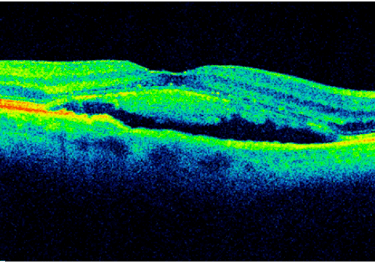

Centralna surowicza chorioretinopatia (CSCR) – aktualny stan wiedzy i opcje terapeutyczne